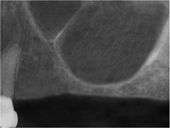

Prior to undergoing sinus augmentation, diagnostics are run to determine the health of the patient’s sinuses. Panoramic radiographs are taken to map out the patient's upper jaw and sinuses. In special instances, a computed tomography or CT scan is taken to measure the sinus’s height and width, and to rule out any sinus disease or pathology.[6]